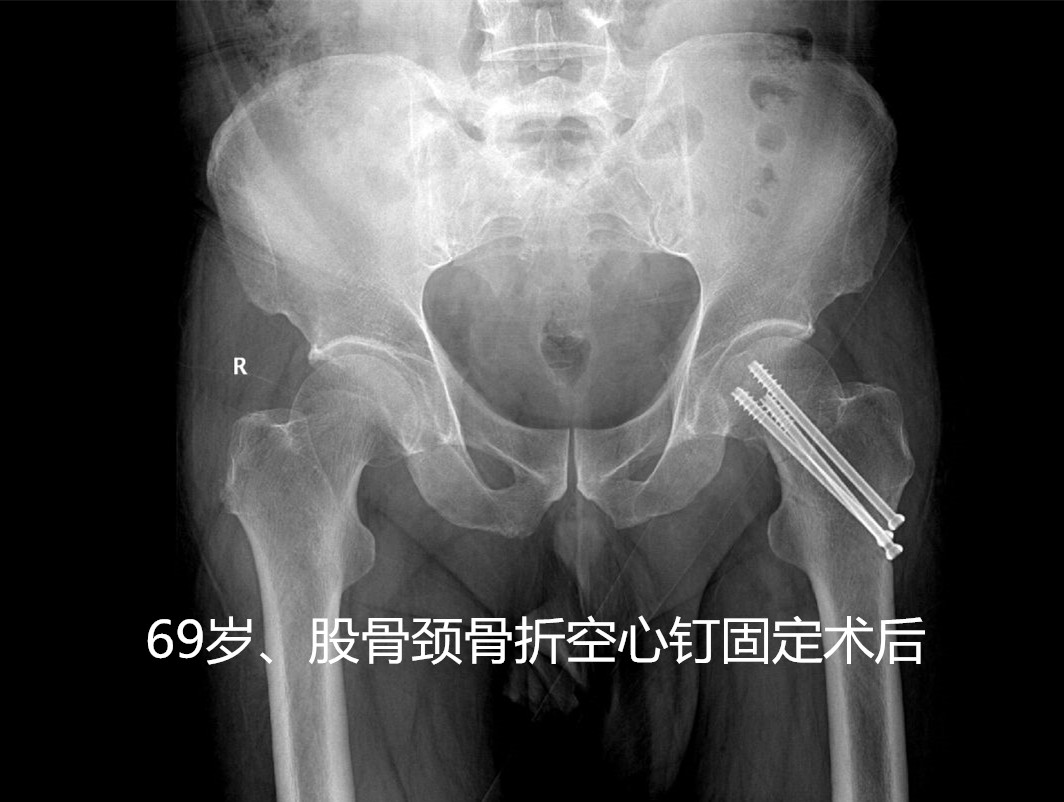

这种骨折出现了怎么治疗呢?其治疗方法分为手术内固定治疗(如空心钉、PFNA、INTER- tan等等)或者人工关节置换手术治疗。

• 对于无移位的股骨颈骨折,可保守治疗,但只要能耐受手术,无绝对手术禁忌症,还是建议手术治疗(如空心钉固定、手术创伤小、费用低),以免卧床期间出现骨折移位,减少卧床时间,便于护理。